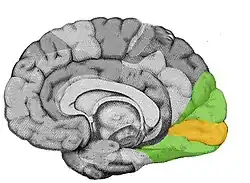

La lesión de cualquiera de las estructuras del sistema visual puede causar ceguera aunque el resto no presente ninguna alteración. En la ceguera cortical, por ejemplo, ocasionada por una lesión en la región occipital del cerebro, se produce pérdida completa de visión aunque el ojo y el nervio óptico no presentan ninguna anomalía.[2][3]

Los axones de las células ganglionares de la retina se reúnen formando el nervio óptico. Los nervios ópticos surgen cerca del polo posterior del ojo y se dirigen hacia atrás y medialmente. Ambos convergen hacia la base del cerebro, donde se unen en una estructura con forma de X, el quiasma óptico, de donde parten las cintillas ópticas que se dirigen a los núcleos geniculados laterales localizados en la cara posterior del tálamo. Las neuronas del núcleo geniculado lateral envían sus axones mediante las llamadas radiaciones ópticas hasta la corteza visual primaria. Aproximadamente el 25 % de la superficie de la corteza visual se dedica al análisis de la información procedente de la fóvea, que representa una parte pequeña del campo visual. Los circuitos neuronales de la corteza visual combinan información de diferentes procedencias y de esta forma integran información más amplia que la que corresponde al campo receptor de una única célula ganglionar. Desde la corteza visual primaria situada en el lóbulo occipital del cerebro parten la corriente visual ventral, que traslada la información hacia la corteza del lóbulo temporal, y la corriente visual dorsal, que la dirige hacia el lóbulo parietal.[7]